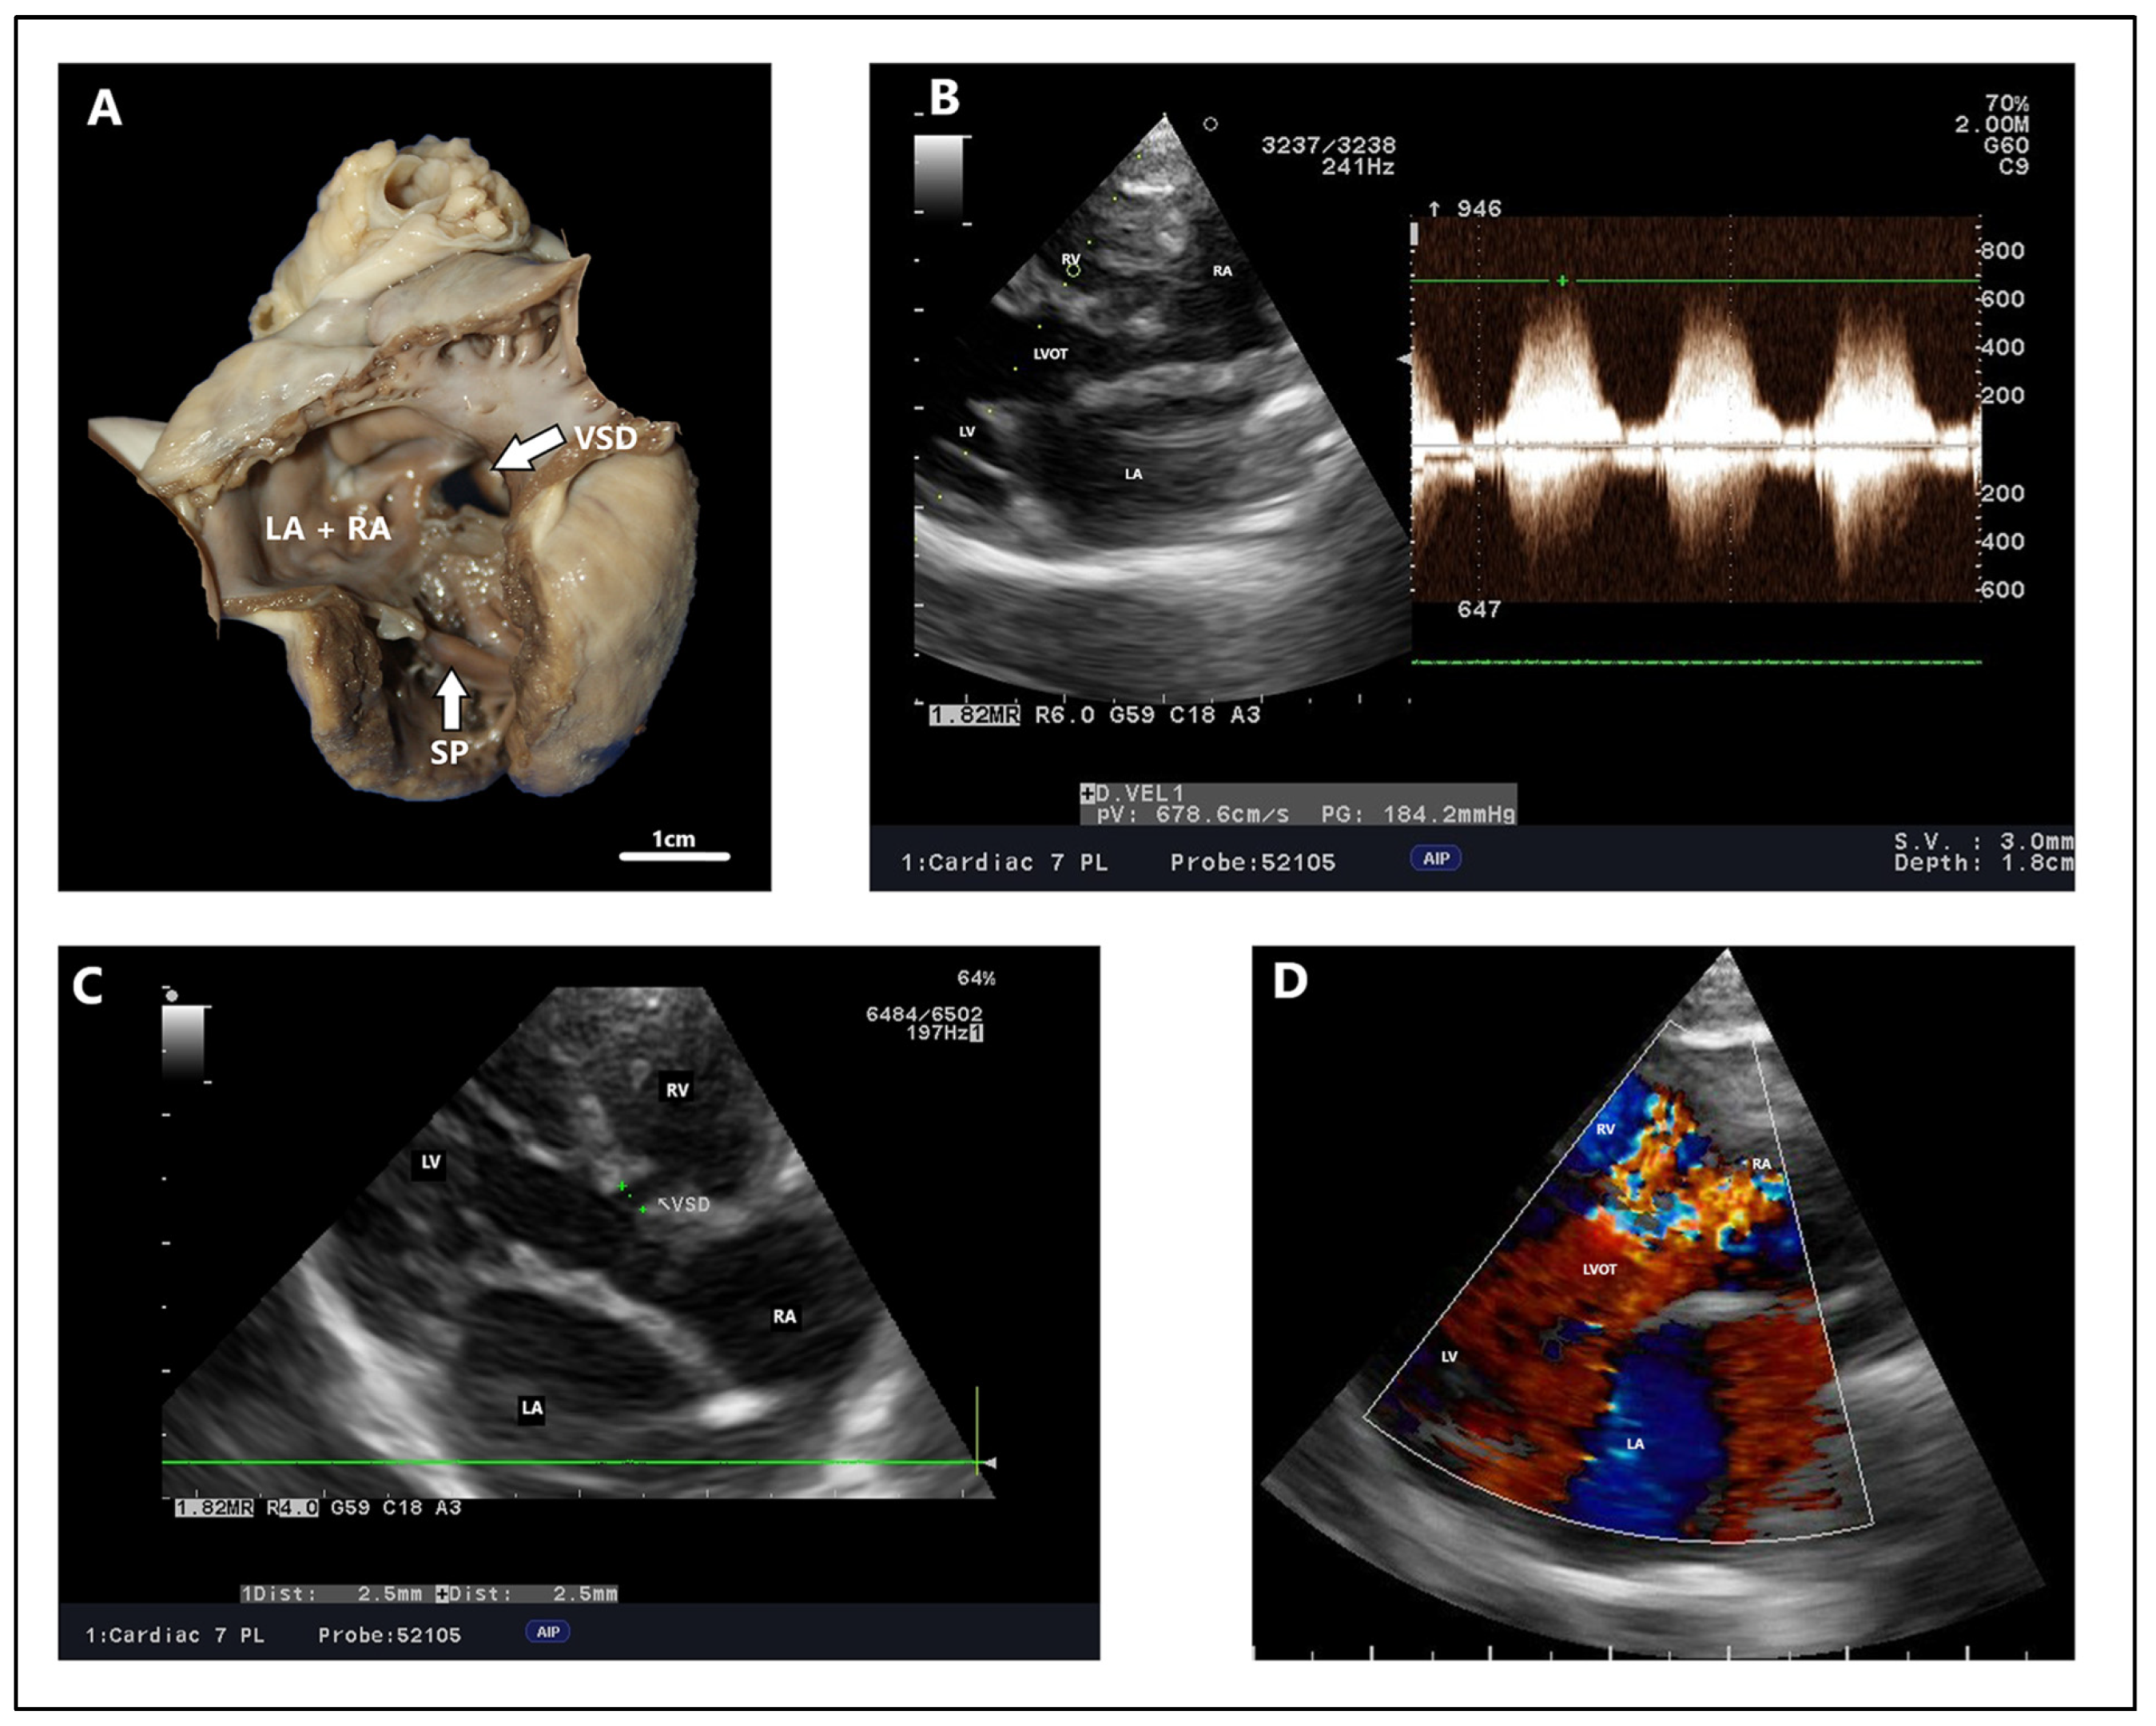

4.2. Echocardiography, Radiography, ECG Findings

- Thomas, W.P. Echocardiographic Diagnosis of Congenital Membranous Ventricular Septal Aneurysm in the Dog and Cat. J. Am. Anim. Hosp. Assoc. 2005, 41, 215–220. [Google Scholar] [CrossRef] [PubMed]